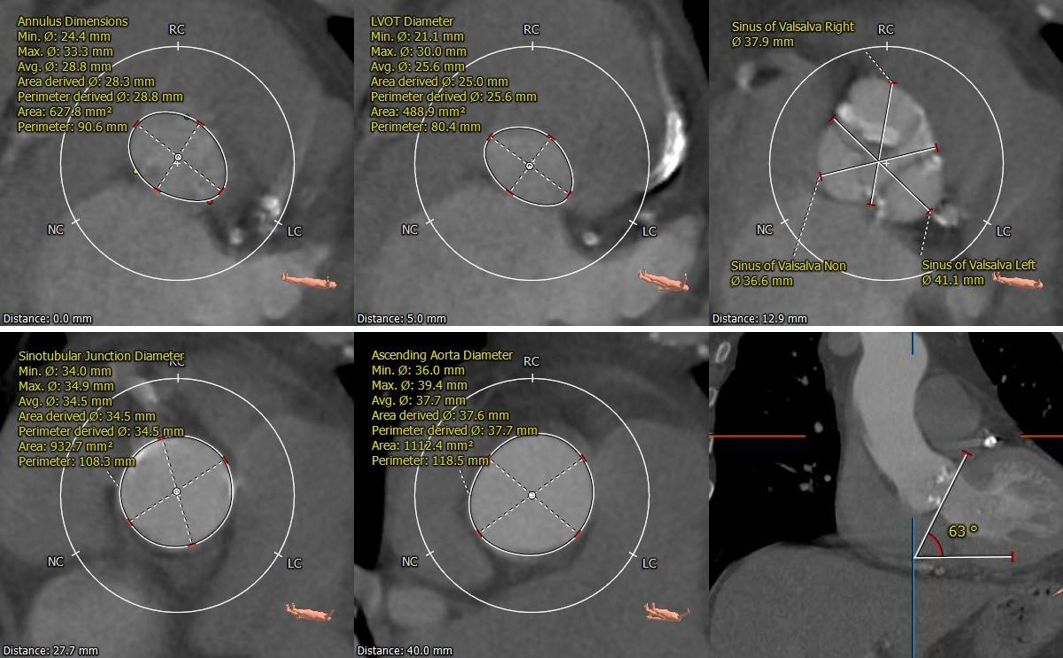

术前CT评估:

主动脉根部评估:

三叶式主动脉瓣,LVOT收口型,横位心。

冠脉评估:

冠脉开口高度可,左冠瓣叶长于开口下缘到附着点距离。

钙化评估:

重度钙化,集中分布于左冠窦、右冠窦内。

入路评估:

外周血管内径可,走形适宜;主动脉弓宽度、夹角可。

CT评估分析